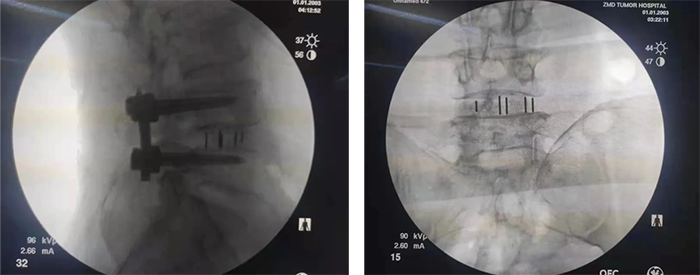

■体外植骨完成,使用半环工作通道进行神经保护,如直接置入,则融合器直接通过工作通道置入即可;如需导针指引,则预先置入导针,透视导针位置,再沿导针置入融合器。

■透视融合器位置,可用打入器进行调整,如有导针,则拔出导针后再调整。

■融合器调整后透视最终位置良好,手术过程完毕,进行最终检查后即可进行置钉操作。